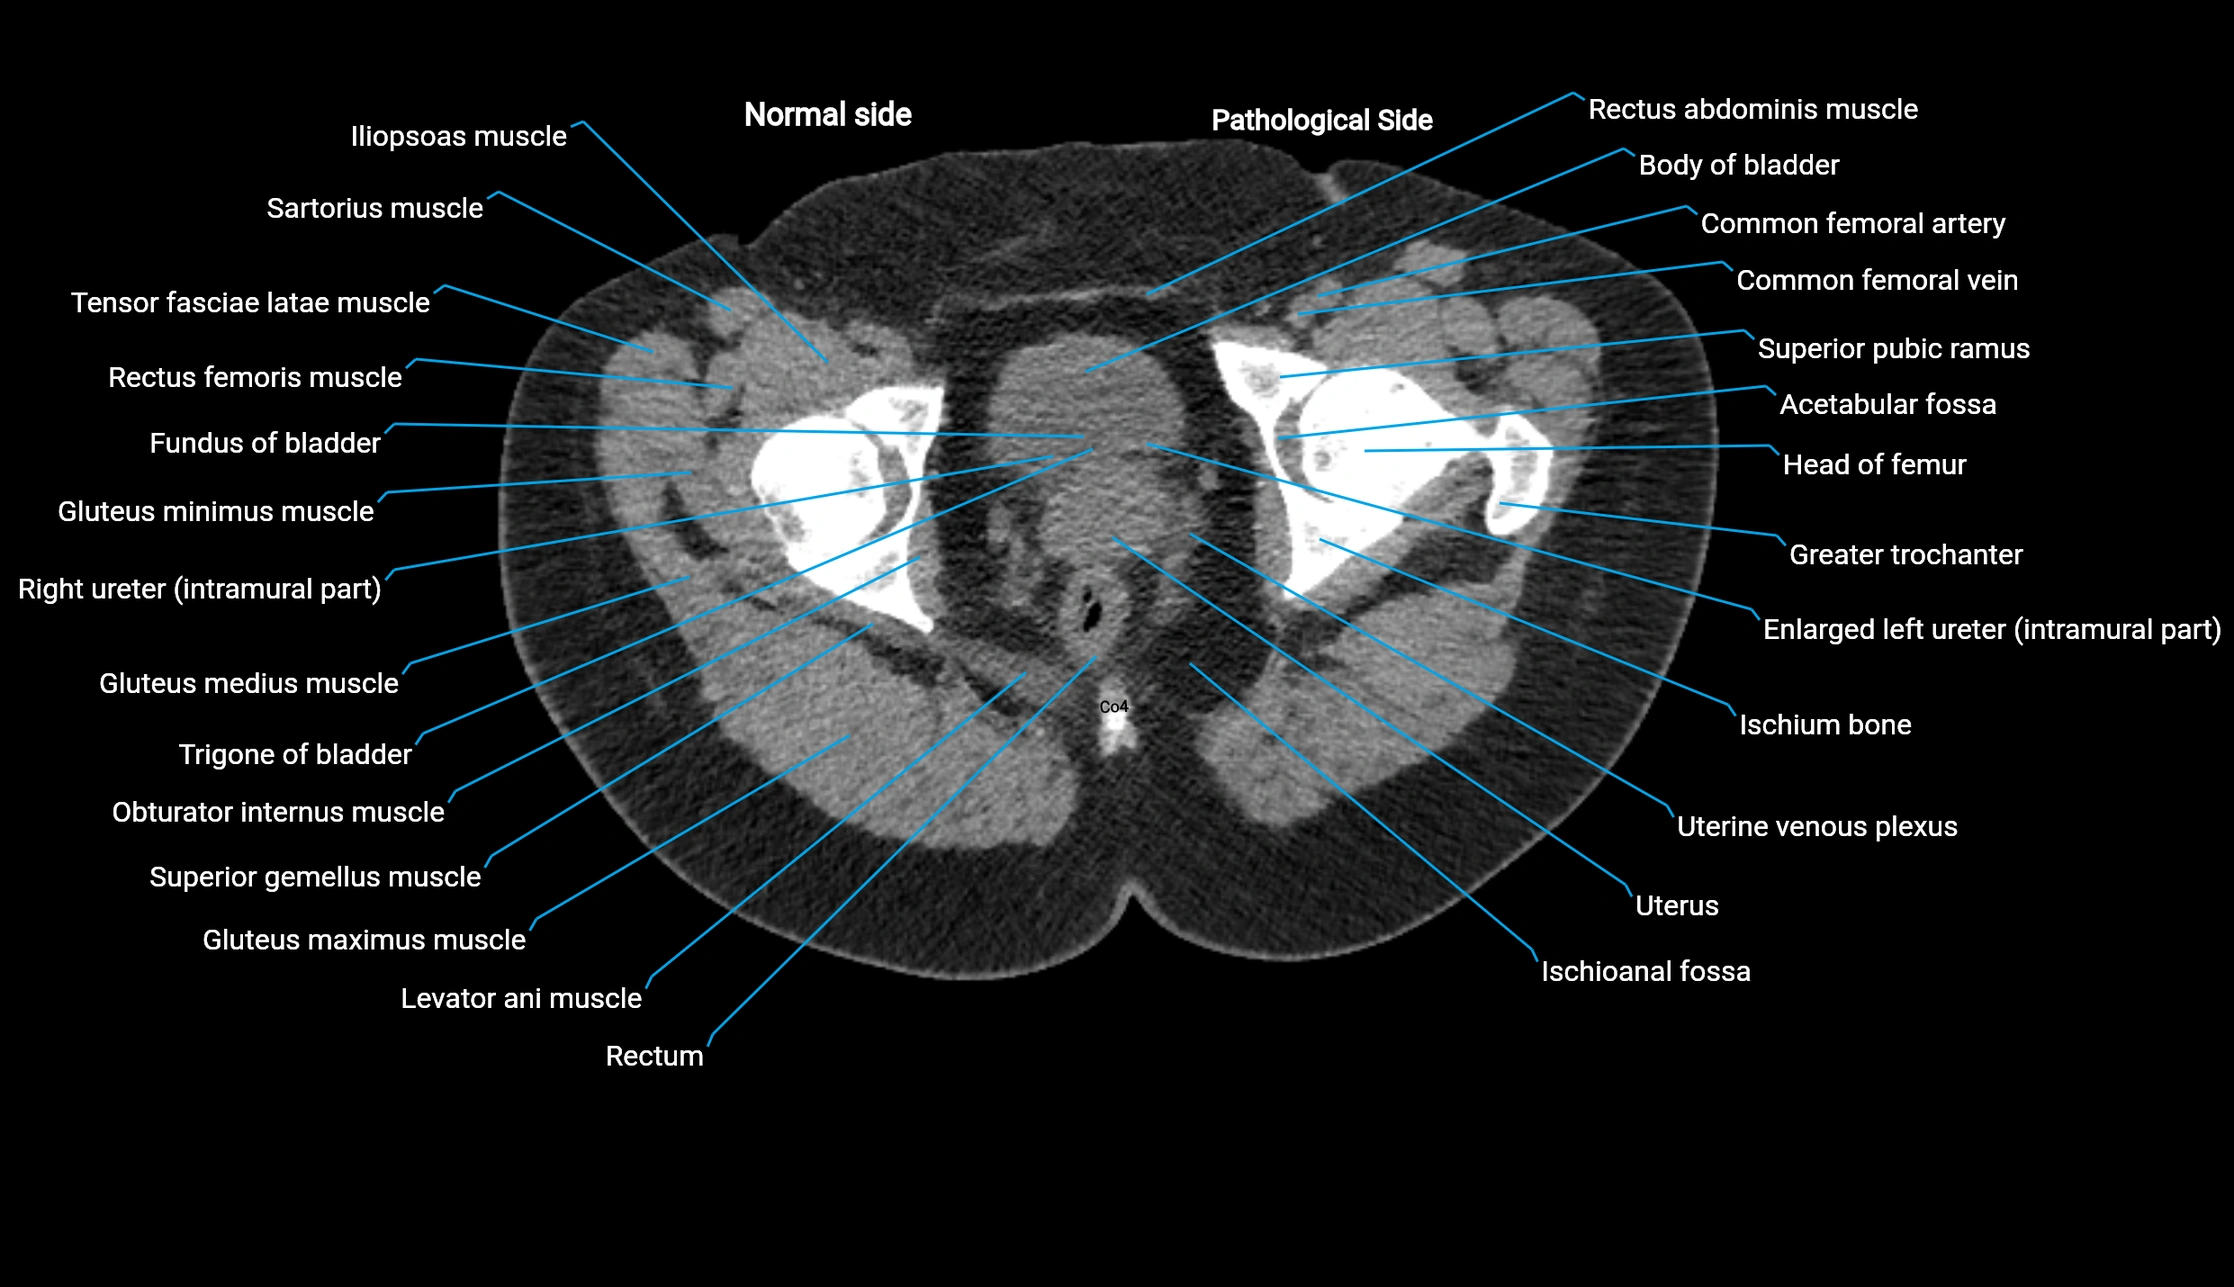

CT image

image